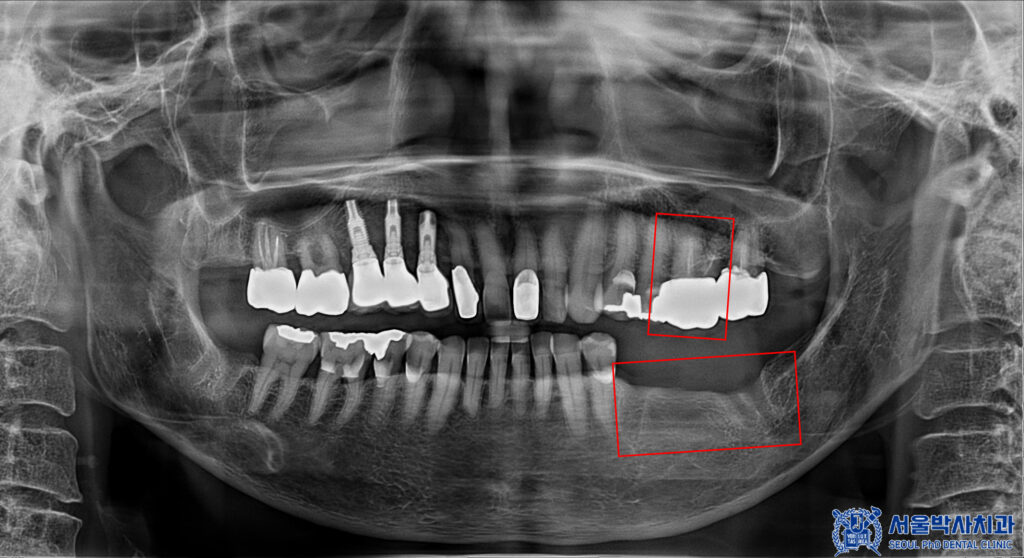

환자분께서는 왼쪽 아래 어금니가

소실된 상태였으며,

왼쪽 위 치아의 보철물 하방으로

충치가 보였습니다.

이러한 경우,

충치 치아 발치 후 상실된 부분을 포함해서

임플란트를 식립 하면 되지만

현재 환자분께서는 골다공증 주사제를

맞고 계신 상태셨습니다.